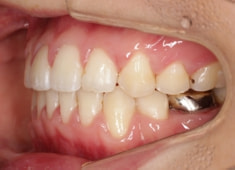

先天欠如歯両側上顎3番

治療法:フルパッシブブラケット:T21

治療開始時